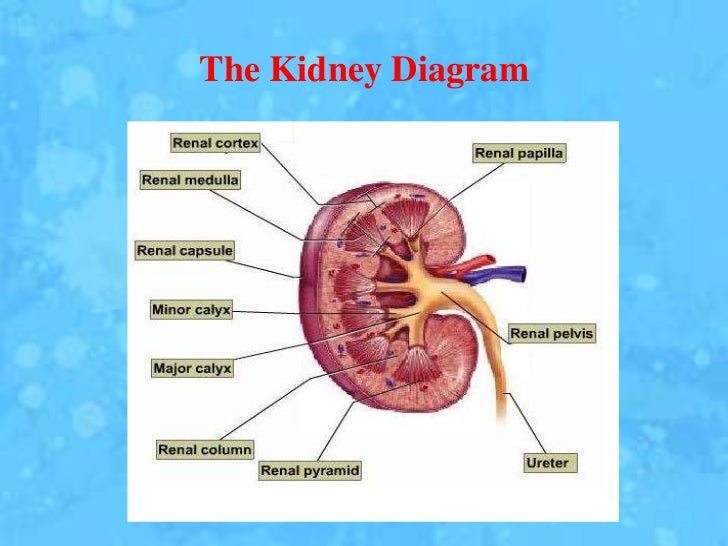

The kidneys are 11 centimeters long paired reddish brown organs situated on the posterior wall of the abdominal cavity one on each side of the vertebral column and capped by the adrenal gland. H ions are produced as a natural byproduct of the metabolism of dietary proteins and accumulate in the blood over time. Connective tissue anchors the kidneys to surrounding structures and helps maintain their normal position.

Upper portions of the kidneys are somewhat protected by the eleventh and twelfth ribs figure 1. Anatomy of the kidneys. Each kidney weighs about 125175 g in males and 115155 g in females.

Due to the presence of the liver the right kidney is slightly lower than the left kidney. They are about 1114 cm in length 6 cm wide and 4 cm thick and are directly covered by a fibrous capsule composed of dense. Anatomy of the urinary system.

The kidneys monitor and regulate the levels of hydrogen ions h and bicarbonate ions in the blood to control blood ph. Glomerular filtration glomerular filtration is the renal process whereby fluid in the blood is filtered across the capillaries of the glomerulus. The right kidney is lower than the left due to displacement by the liver.